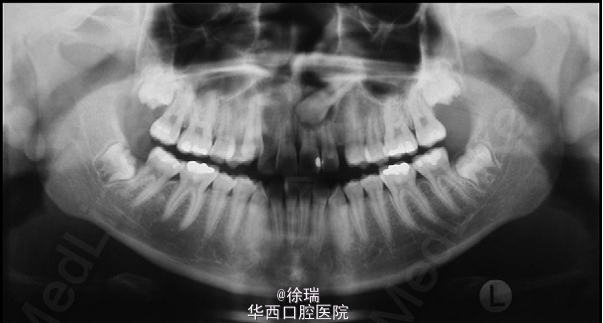

论早期诊断异位尖牙的重要性

徐助教   四川大学华西口腔医院

尖牙的异位萌出多见于上颌,可造成相邻牙齿的根尖吸收。最近遇到了一个病例,15岁的女孩儿,安氏III类,上颌尖牙阻生,因为尖牙的位置太过靠近侧切牙和中切牙根方,邻牙发生了严重的根尖吸收。那这样的病情又该如何矫正呢?